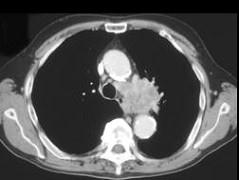

男,59岁,咳嗽,咳痰,痰中带血2月余,CT检查如图,请选出最可能的诊断 ( )A、肺炎B、肺错构瘤C、中央型肺癌D、矽肺E、肺结核

问题 男,59岁,咳嗽,咳痰,痰中带血2月余,CT检查如图,请选出最可能的诊断 ( )

选项 A、肺炎 B、肺错构瘤 C、中央型肺癌 D、矽肺 E、肺结核

答案 C